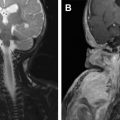

The most common vascular tumors consist of infantile hemangioma (IH), congenital hemangioma (CH), pyogenic granuloma, and kaposiform hemangioendothelioma (KHE) ( Fig. 1 ). Malformations are divided into rheologically slow-flow lesions (CM, VM, LM) or fast-flow anomalies (AVM, arterial aneurysm/atresia/ectasia/stenosis) ( Fig. 2 ). Combined vascular anomalies, most commonly lymphatic venous malformation, can also occur. Eponymous syndromes that include vascular anomalies exist; one example is Klippel-Trénaunay syndrome, a capillary lymphatic venous malformation of an extremity with overgrowth.